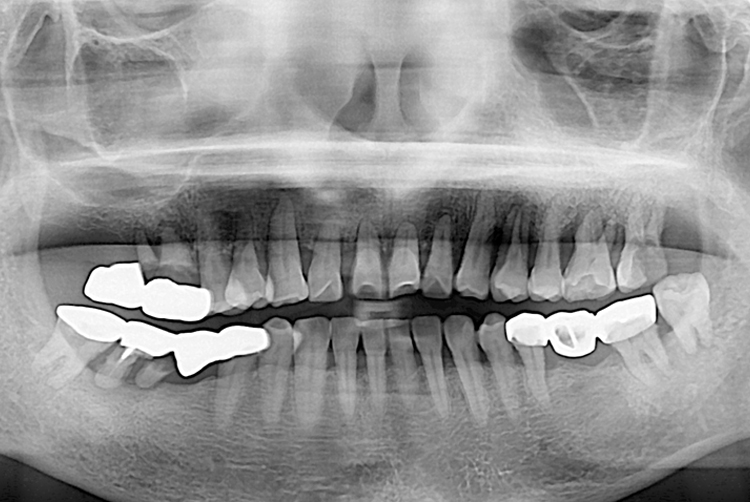

[임플란트] 임플란트

이숙자_후.jpg

치료후 : 2019-06-05

세종치과는 많은 환자와 다양한 케이스를 바탕으로 항상 편안한 임플란트 수술을 제공하고자 노력하고,

오래동안 튼튼히 쓸 수 있는 임플란트 수술을 가장 큰 목표로 삼고 있습니다